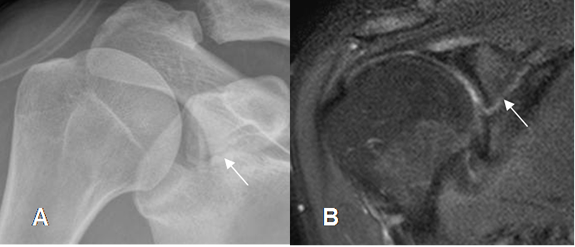

Fig 59. Fractura de escápula.

A: Rx AP de hombro y B: RM coronal en STIR. Fractura oblicua de la glenoides.